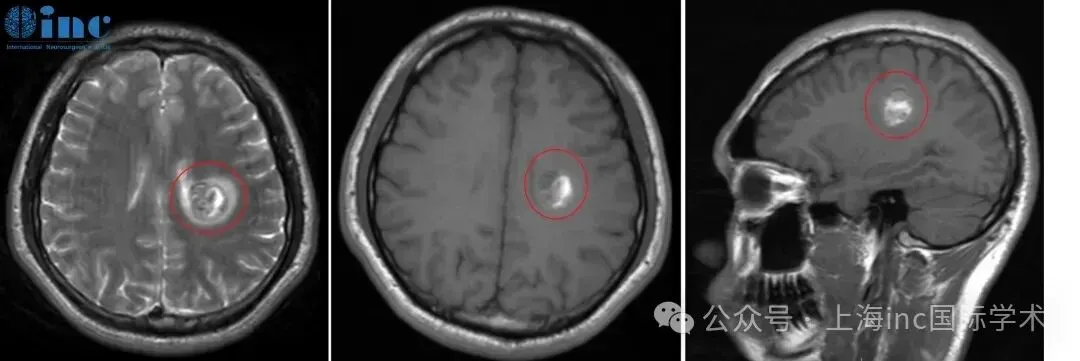

一年前,30岁患者阿勇出现右手握笔障碍,书写字迹逐渐扭曲,伴右侧肢体提重物时无力感。症状持续半月后就诊,MRI检查显示左侧半卵圆中心区存在8.0×11.0mm类圆形异常信号灶,初步诊断为功能区海绵状血管瘤。2022年5月MRI影像证实病灶处于急性出血期,提示若未及时干预,再次出血可能导致右手完全瘫痪及语言功能受损。